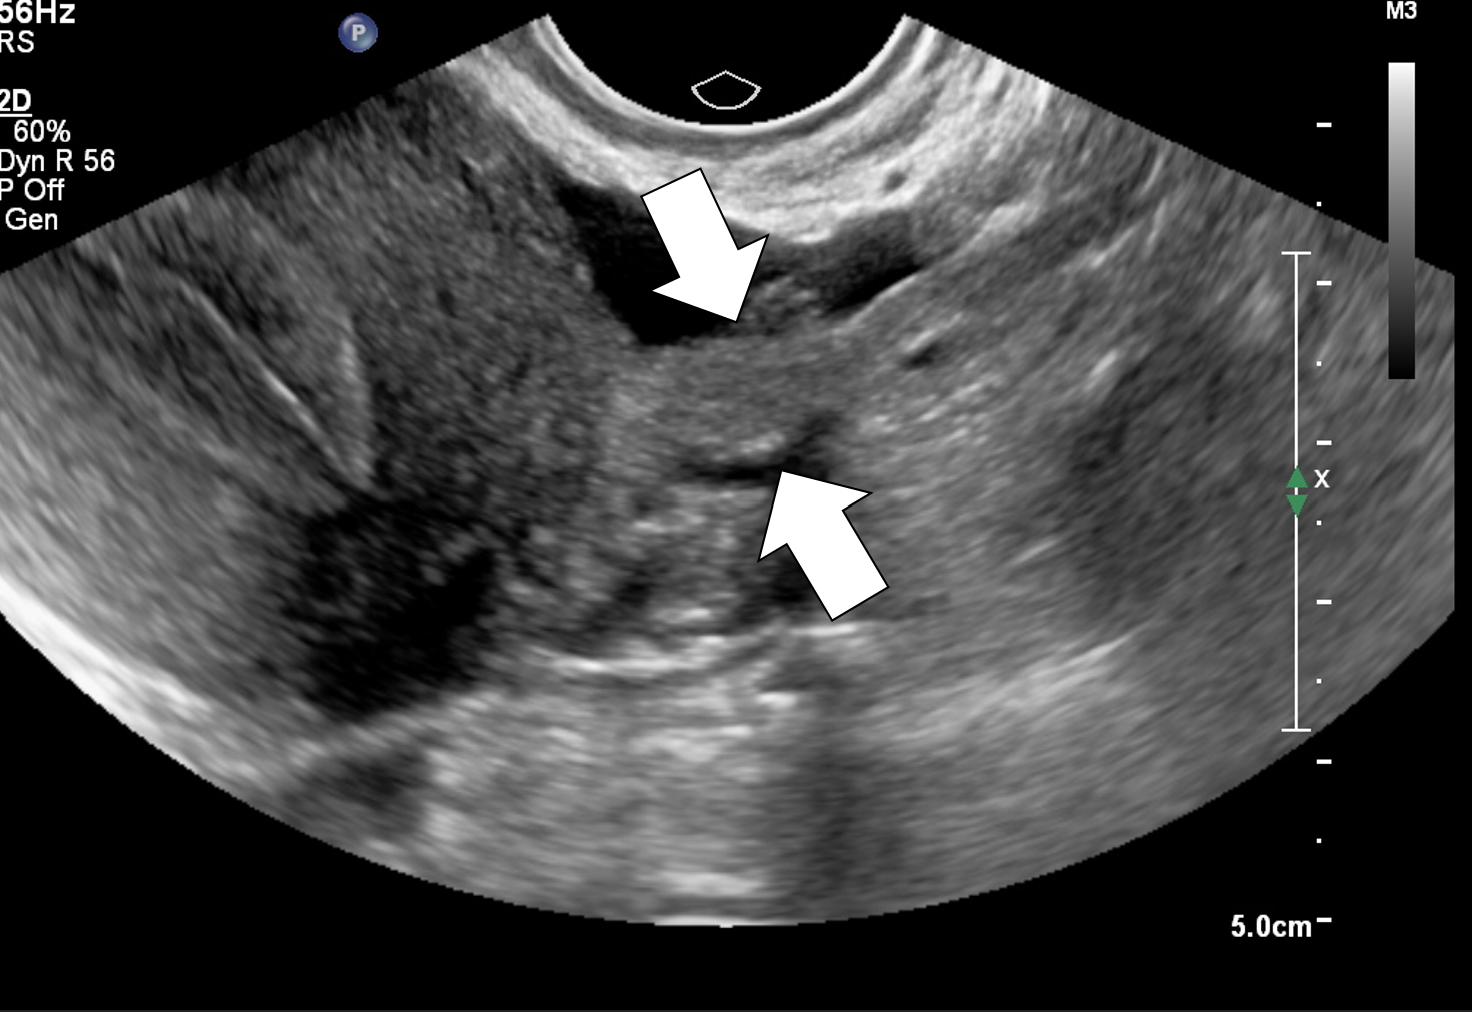

cisto_hemorragico_reticular

Ultrassonografia transvaginal. Observa-se formação cística anexial com conteúdo interno heterogêneo, apresentando finos ecos e padrão reticular (aspecto em “rede”/fibrina), sem componentes sólidos verdadeiros. Achados característicos de cisto hemorrágico ovariano.